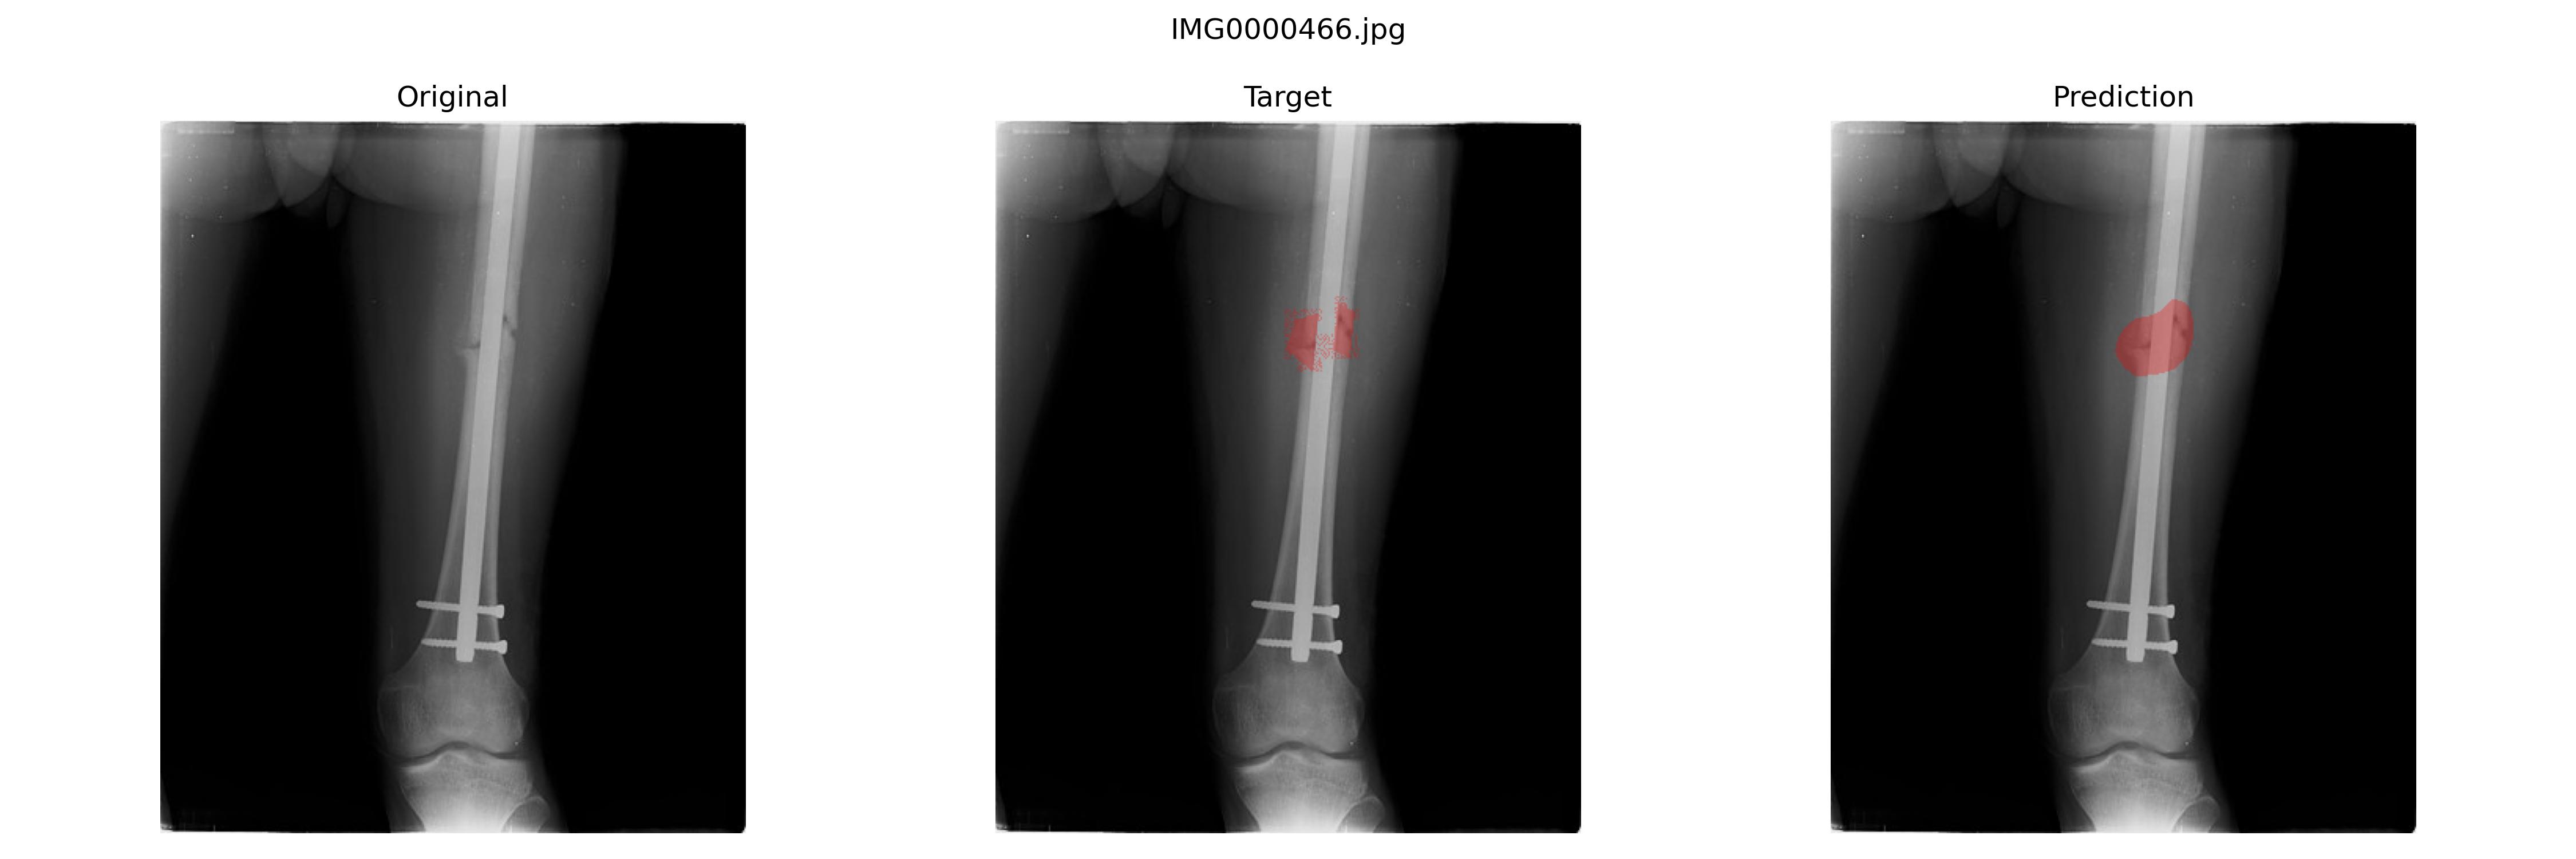

结果预览

二者其实差不多嘛

经过多次实验,最好的模型是U+net+Dice loss

1

epoch:133,sensitivity(Recall):0.904,specificity:0.981,precision:0.849